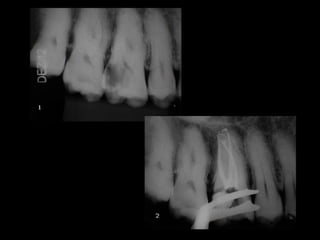

• #16 A RX revela um 1º molar inferior direito com lesão periapical e lesão de furca. Protocolo de tratamento: Ler o slide. Comentário: Limiar de infecção é o número de micro-organismos necessários para causar uma lesão periapical ou 1. Para surgir uma lesão periapical num dente com necrose e infecção há necessidade de de um número de bctérias acima do limiar de infecção.